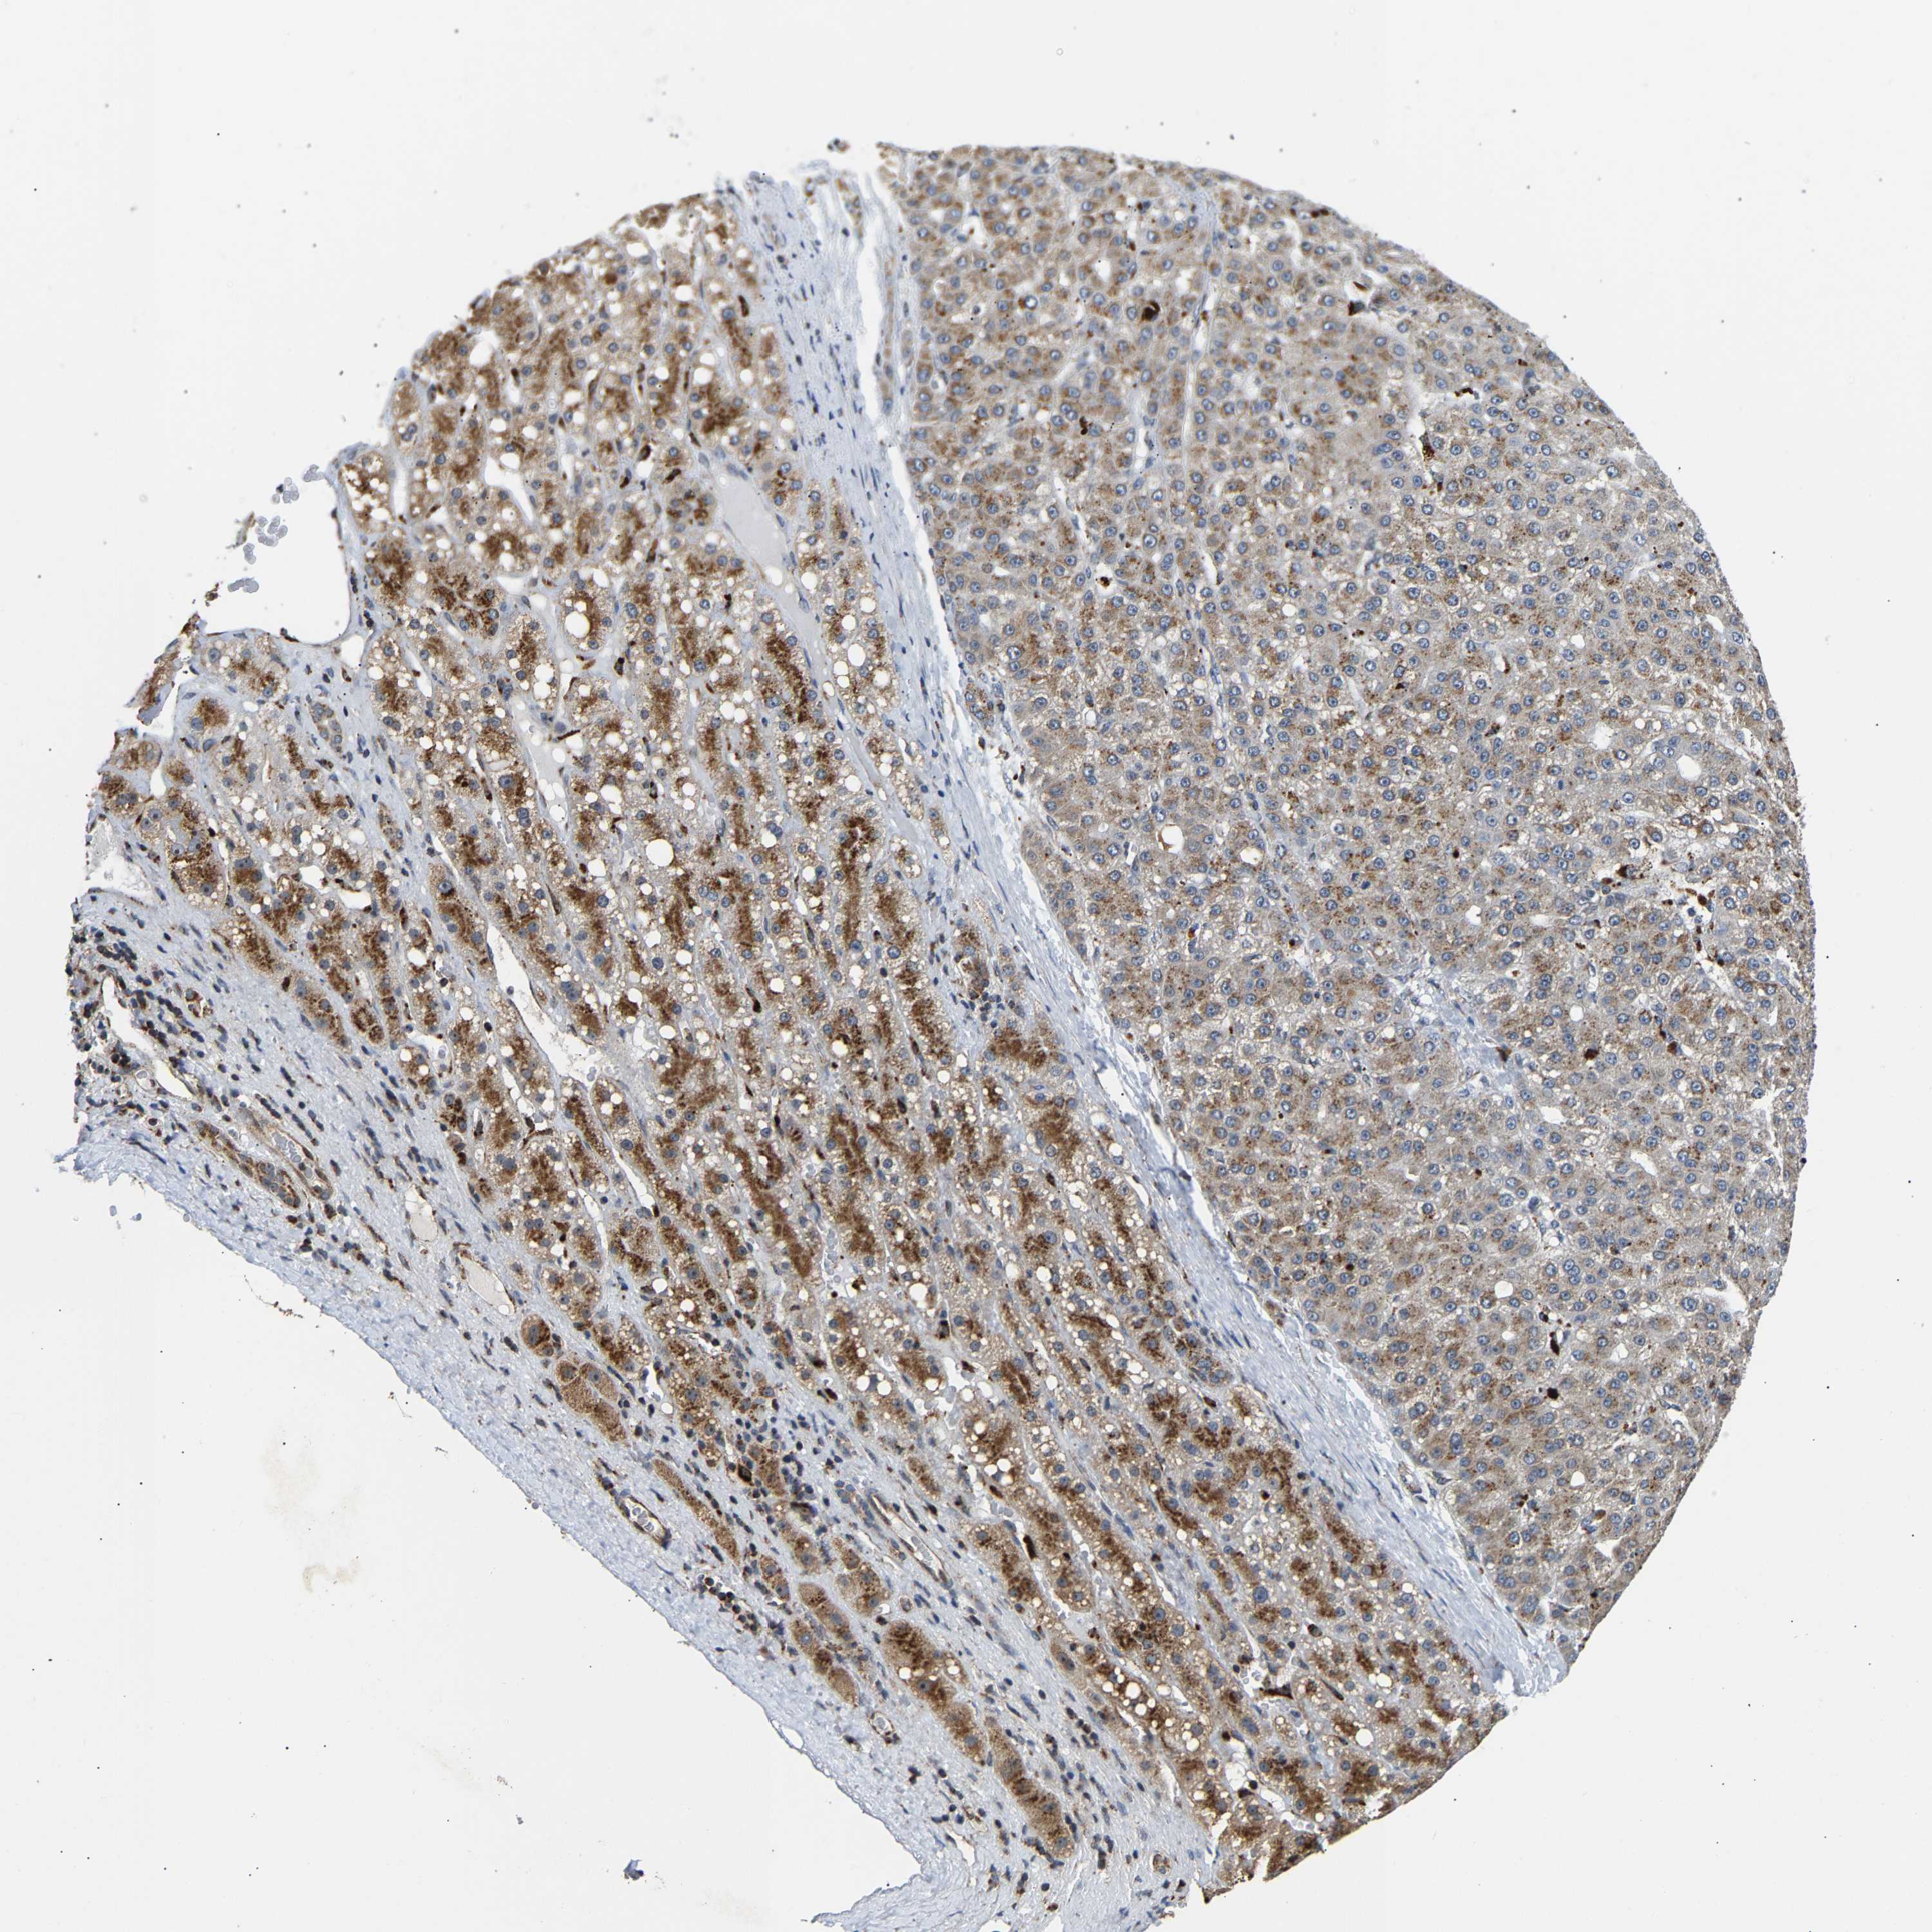

LIVER CANCER - Protein expressioni

A mouse-over function shows sample information and annotation data. Click on an image to view it in a full screen mode. Samples can be filtered based on level of antibody staining by selecting one or several of the following categories: high, medium, low and not detected. The assay and annotation is described here.

Note that samples used for immunohistochemistry by the Human Protein Atlas do not correspond to samples in the TCGA dataset.

Antibody stainingi

Antibody staining in the annotated cell types in the current human tissue is reported as not detected, low, medium, or high, based on conventional immunohistochemistry profiling in selected tissues. This score is based on the combination of the staining intensity and fraction of stained cells.

Each image is clickable and will lead to virtual microscopy that enables deeper exploration of all samples and also displays staining intensity scores, fraction scores and subcellular localization as well as patient and tissue information for each sample.

Antibody HPA020266

Antibody HPA020268

Staining

High

Medium

Low

Not detected

Intensity

Strong

Moderate

Weak

Negative

Quantity

>75%

75%-25%

<25%

None

Location

Nuclear

Cytoplasmic/membranous

Cytoplasmic/membranous,nuclear

Cholangiocarcinoma

Carcinoma, Hepatocellular, NOS